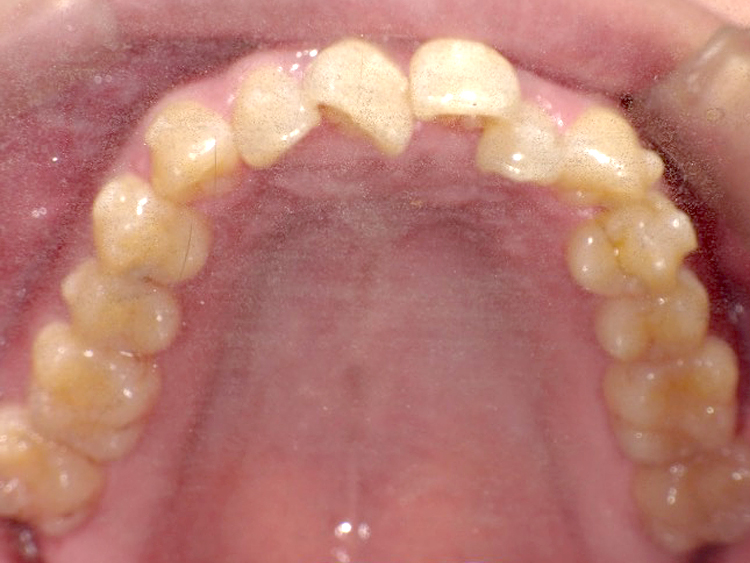

症例4

Before

After

| 主訴 | 上下前歯のがたつき |

|---|---|

| 年齢 | --- |

| 治療 期間 |

約9ヶ月 |

| 治療 内容 |

インビザラインiGoで上下顎の治療。 |

| 治療費 | ¥550,000(税込)/調整料含む |

| 治療のリスク | 矯正終了後は、リテーナーを指示通りに使用し、歯の後戻りを防ぐ必要があります。 |